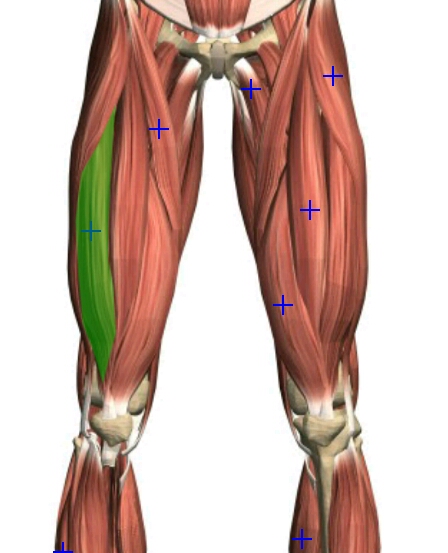

Cara Mudah Nak Kurangkan Sakit Lutut, Kaki & Pinggul Dengan 7 Latihan Efektif Ini! - MASKULIN

Cara Mudah Nak Kurangkan Sakit Lutut, Kaki & Pinggul Dengan 7 Latihan Efektif Ini! - MASKULIN

Cara Mudah Nak Kurangkan Sakit Lutut, Kaki & Pinggul Dengan 7 Latihan Efektif Ini! - MASKULIN

Cara Mudah Nak Kurangkan Sakit Lutut, Kaki & Pinggul Dengan 7 Latihan Efektif Ini! - MASKULIN